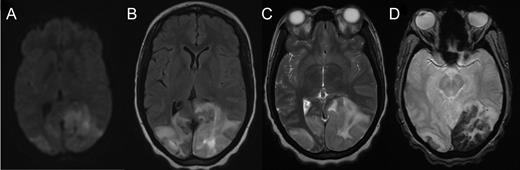

Axial MRI demonstrating cerebral tissue injuries from venous hypertension with the associated ischemia: (A) Diffusion-weighted imaging (DWI) MRI. (B) Fluid-attenuated inversion recovery (FLAIR) imaging. (C) T2-weighted MRI. (D) Gradient-echo (GRE) imaging.

Dural sinus venogram (A) Prior to endovascular mechanical thrombectomy (B) Post mechanical thrombectomy. (C) Pre-intervention MRV demonstrating complete occlusion of the left transverse sinus and near occlusion of the posterior portion of the superior sagittal sinus. (D) Post-intervention MRV demonstrating persistent recanalization of the left transverse and sigmoid sinuses, along with much improved flow in the posterior superior sagittal sinus. Note the recanalization of the left transverse sinus and the much improved flow in the superior sagittal sinus.

The patient was treated emergently with endovascular mechanical thrombolysis with technical success (Fig. 3A and B), followed by systemic anticoagulation therapy. Post-intervention MRV demonstrated persistent recanalization of the left transverse and sigmoid sinuses, along with much improved flow in the posterior superior sagittal sinus (Fig. 3D).